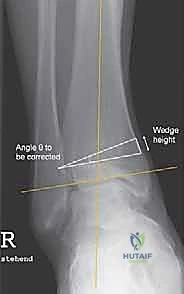

- الأشعة السينية أثناء الوقوف (Weight-Bearing X-rays): هذه هي الخطوة الأهم. لا يمكن تقييم تشوه الكاحل بدقة والمريض مستلقٍ. يجب أخذ صور أشعة طويلة للساقين بالكامل لتحديد "محور التحميل الميكانيكي" وقياس زوايا التشوه بدقة متناهية (مثل زاوية TAS وزاوية TLS).

النجاح في عملية قطع العظم فوق الكاحل لا يحدث بالصدفة، بل هو نتيجة تخطيط هندسي وبيوميكانيكي دقيق قبل دخول غرفة العمليات. يقوم الدكتور محمد هطيف باستخدام برامج كمبيوتر متخصصة لتحليل صور الأشعة الخاصة بالمريض. يتم حساب الزوايا بدقة تصل إلى كسور الدرجة، وتحديد مكان القص الجراحي (Osteotomy site) بشكل مثالي.